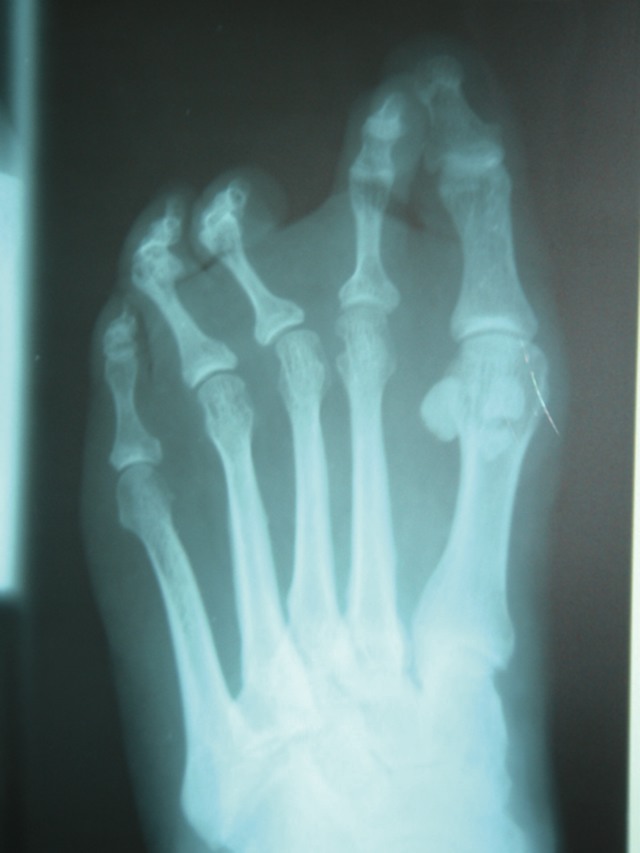

One would perform the osteotomy at an acute and fairly horizontal angle to the ground and metatarsal shaft, allowing for a generous cortical cancellous shelf amenable to screw fixation. When dealing with concomitant plantar keratoma or a planned metatarsal head length reduction beyond 5 mm, the podiatric surgeon should consider using a thicker saw blade to produce more significant reduction of plantar pressure.6,7 Once one has obtained satisfactory anesthesia, approach the metatarsophalangeal joint through a dorsal curve linear or serpentine incision. Doing so can help prevent scar contracture that can contribute to floating toe syndrome and extension contracture. Place the incision centrally over the joint with a length of approximately 3 cm. The surgeon can easily extend the incision distally to manage complex digital deformities. When addressing adjacent metatarsal deformities, you may elect to employ a two incision or a single interspace approach. Depending on one’s preference, the surgeon would divide the soft tissues to expose the dorsal surface of the metatarsophalangeal joint. Perform a linear capsulotomy sharply either medial or lateral to the long extensor tendon. Leave the extensor tendon intact at this point and address any remaining soft tissue contracture after the osteotomy fixation through additional extensor tendon or capsule lengthening. We typically employ a dorsal medial incision to the second and third metatarsals, and employ a lateral dorsal capsulotomy for the fourth and fifth metatarsals. Capsular dissection begins at the dorsal base of the proximal phalanx. After exposing the base, utilizing minimal periosteal dissection facilitates very adequate exposure to the distal metatarsal neck and maintains blood supply at the osteotomy site. Leave the collateral suspensory ligaments intact unless there is significant plantar plate disruption with complex hammertoe deformity. The most common goal of the Weil osteotomy is to produce offloading of plantar metatarsal head pressure. Variables such as the osteotomy angle, saw blade thickness, capital fragment shortening, angulation or transposition can have a direct impact on osteotomy performance. Preoperative standard radiographs are invaluable at assessing metatarsal parabola length for surgical planning. Intraoperative fluoroscopy allows immediate decision making to obtain the appropriate metatarsal reduction. Once proper soft tissue retraction is in place, it is common to employ a small sagittal saw with a #138 Hall blade (Zimmer). The osteotomy begins in the dorsal 2 to 3 mm range of the distal articular cartilage. The surgeon typically makes the osteotomy at an angle of 10 to 15 degrees to the metatarsal shaft. Preoperative assessment of the metatarsal declination can alter the orientation of the osteotomy relative to the ground.6,8 The cascading effect is most apparent with the decrease in metatarsal declination from the second to fifth metatarsals. One would perform the osteotomy in the transverse plane in a complete manner with a well irrigated sagittal saw. After completing the osteotomy, a “proximal release” of the plantar capital fragment occurs. This facilitates decompression of the joint. If preoperative planning calls for greater than 5 mm of length decompression or the metatarsal declination is flat (15 to 17 inches), the surgeon should consider doubling the osteotomy thickness with two parallel blades on the sagittal saw. This technique is effective for more aggressive offloading of the metatarsal head fragment. Remodel the dorsal metatarsal overhang with a rongeur and rotary burr. Reposition the capital fragment 3 to 5 mm proximally. Additionally, one can transpose the osteotomy or angulate it medially or laterally to correct and balance varus and valgus deformities. Manually compress the osteotomy with plantar digital pressure and temporarily fixate it with one or two 0.045 K-wires. Once you have established temporary fixation, use intraoperative fluoroscopy to confirm the desired position. Spot fluoroscopy can significantly help the surgeon to determine capital fragment placement, especially when one is performing multiple metatarsal osteotomies.

There are a variety of options for fixation of the Weil osteotomy. The osteotomy procedure creates a generous plantar shelf, which allows bicortical fixation. However, the surgeon may choose to fixate the fragment into the cancellous head for effective corticocancellous fixation. Hybrid metatarsal screw fixation allows the foot surgeon to employ a single screw in either of these situations. When it comes to fixation, I prefer to use a 2.0 titanium Charlotte Snap-Off Screw System (Wright Medical) and a more vertical orientation. Apply the 0.045 K-wire for temporary fixation. This serves as a drill hole for the 2.0 hybrid screw. Place the screw manually with a screwdriver in a clockwise manner into the guide hole and advance it through the periosteum, engaging the two fragments with “two finger tightness.” If one does not employ a second K-wire, the osteotomy may rotate in a clockwise manner with screw application. One may place a periosteal elevator on the right side of the metatarsal head to provide counter pressure and prevent rotation. Additionally, the surgeon should provide digital pressure on the plantar skin to ensure further stability while applying the screw. One would typically place the screw 5 mm proximal to the osteotomy. Surgeons may add a second screw for additional stability of a more complex osteotomy with varus or valgus translation or medial or lateral transposition. Once you have established rigid fixation and verified it with fluoroscopy, assess the joint’s range of motion. Additional trimming of the dorsal overhang or the dorsal base of the proximal phalanx helps to prevent dorsal intrusion or jamming of the surgically altered joint. Irrigate the wound and approximate the dorsal capsule. At this time, one can address appropriate additional lengthening of the extensor tendon as well as digital deformities.

Lesser metatarsal osteotomies are effective for a variety of indications. Most commonly, forefoot pain is the culprit and can occur from long-term metatarsophalangeal joint instability. One needs to properly assess the unstable MPJ. A digital Lachman test can give the surgeon an indication of the integrity of a plantar plate MPJ injury. Be aware that sagittal plane forefoot deformities with dorsal subluxation of the phalanx and concurrent hammertoe deformity can be further compounded with digital varus or valgus overlap deformity. Lesser MPJ disorders may also involve hindfoot deformities of equinus, varus or valgus hindfoot, hypermobility and degenerative joint disease. The Weil osteotomy with capsulotendon balancing and digital fusion can provide the surgeon with a variety of modifications to address complex lesser metatarsal issues. When weighing single or multiple lesser metatarsal osteotomies, foot and ankle surgeons may consider hybrid screw fixation techniques that allow early weightbearing, joint mobilization and effective interfragmentary compression with a low screw failure rate. The screw fixation system should offer the surgeon flexibility in applications, simplicity in design, self tapping, a low profile screw head design and a variety of lengths and widths for metatarsal osteotomy fixation. The aforementioned Snap-Off screw is available in 2.0 mm and 2.7 mm diameters in lengths ranging from 11 mm to 17 mm. Surgeons most commonly employ the 2.0 mm Snap-Off screw in lesser metatarsal surgery. The 2.0 mm screw application is also indicated for tailor bunion repair with either a mini-Z or mini-Chevron osteotomy. The 2.0 mm screws come in lengths of 11 mm, 12 mm and 14 mm. Additionally, the screw design lends creates lag compression with a self tapping design. The Weil osteotomy creates a generous metaphyseal and diaphyseal surface that is stable in the sagittal plane. Ground reactive forces naturally aid in compression of the two fragments. One may perform hybrid screw fixation in a cortical metaphyseal manner by applying the 2.0 mm Snap-Off screw distal oblique into the metatarsal head. Obtain bicortical fixation by purchasing the plantar cortex with a vertically placed screw. In either style of fixation, apply temporary stabilization through two cortices vertically with a 0.045 K-wire. If you are performing multiple metatarsal osteotomies, establish the new metatarsal parabola as per your preference with similar 0.045 K-wires for stabilization. One can easily visualize the metatarsal parabola on digital intraoperative fluoroscopy and adjust it accordingly. One can place a second K-wire for secondary stabilization. The 0.045 K-wire serves as a drill hole for application of a 2.0 Snap-Off screw. Apply the pre-drilling technique through both near and far cortical surfaces. Manually apply the screw through the periosteum with two finger tightness. Pre-drilling with a 0.045 K-wire also reduces clockwise rotation and eliminates distraction of the distal fragment. Typically, I choose a 14 mm 2.0 Snap-Off screw for second and third metatarsal osteotomies. The surgeon typically performs fourth metatarsal osteotomy fixation with 2x blade sagittal saw thickness and fixate it with a 12 mm 2.0 Snap-Off screw.